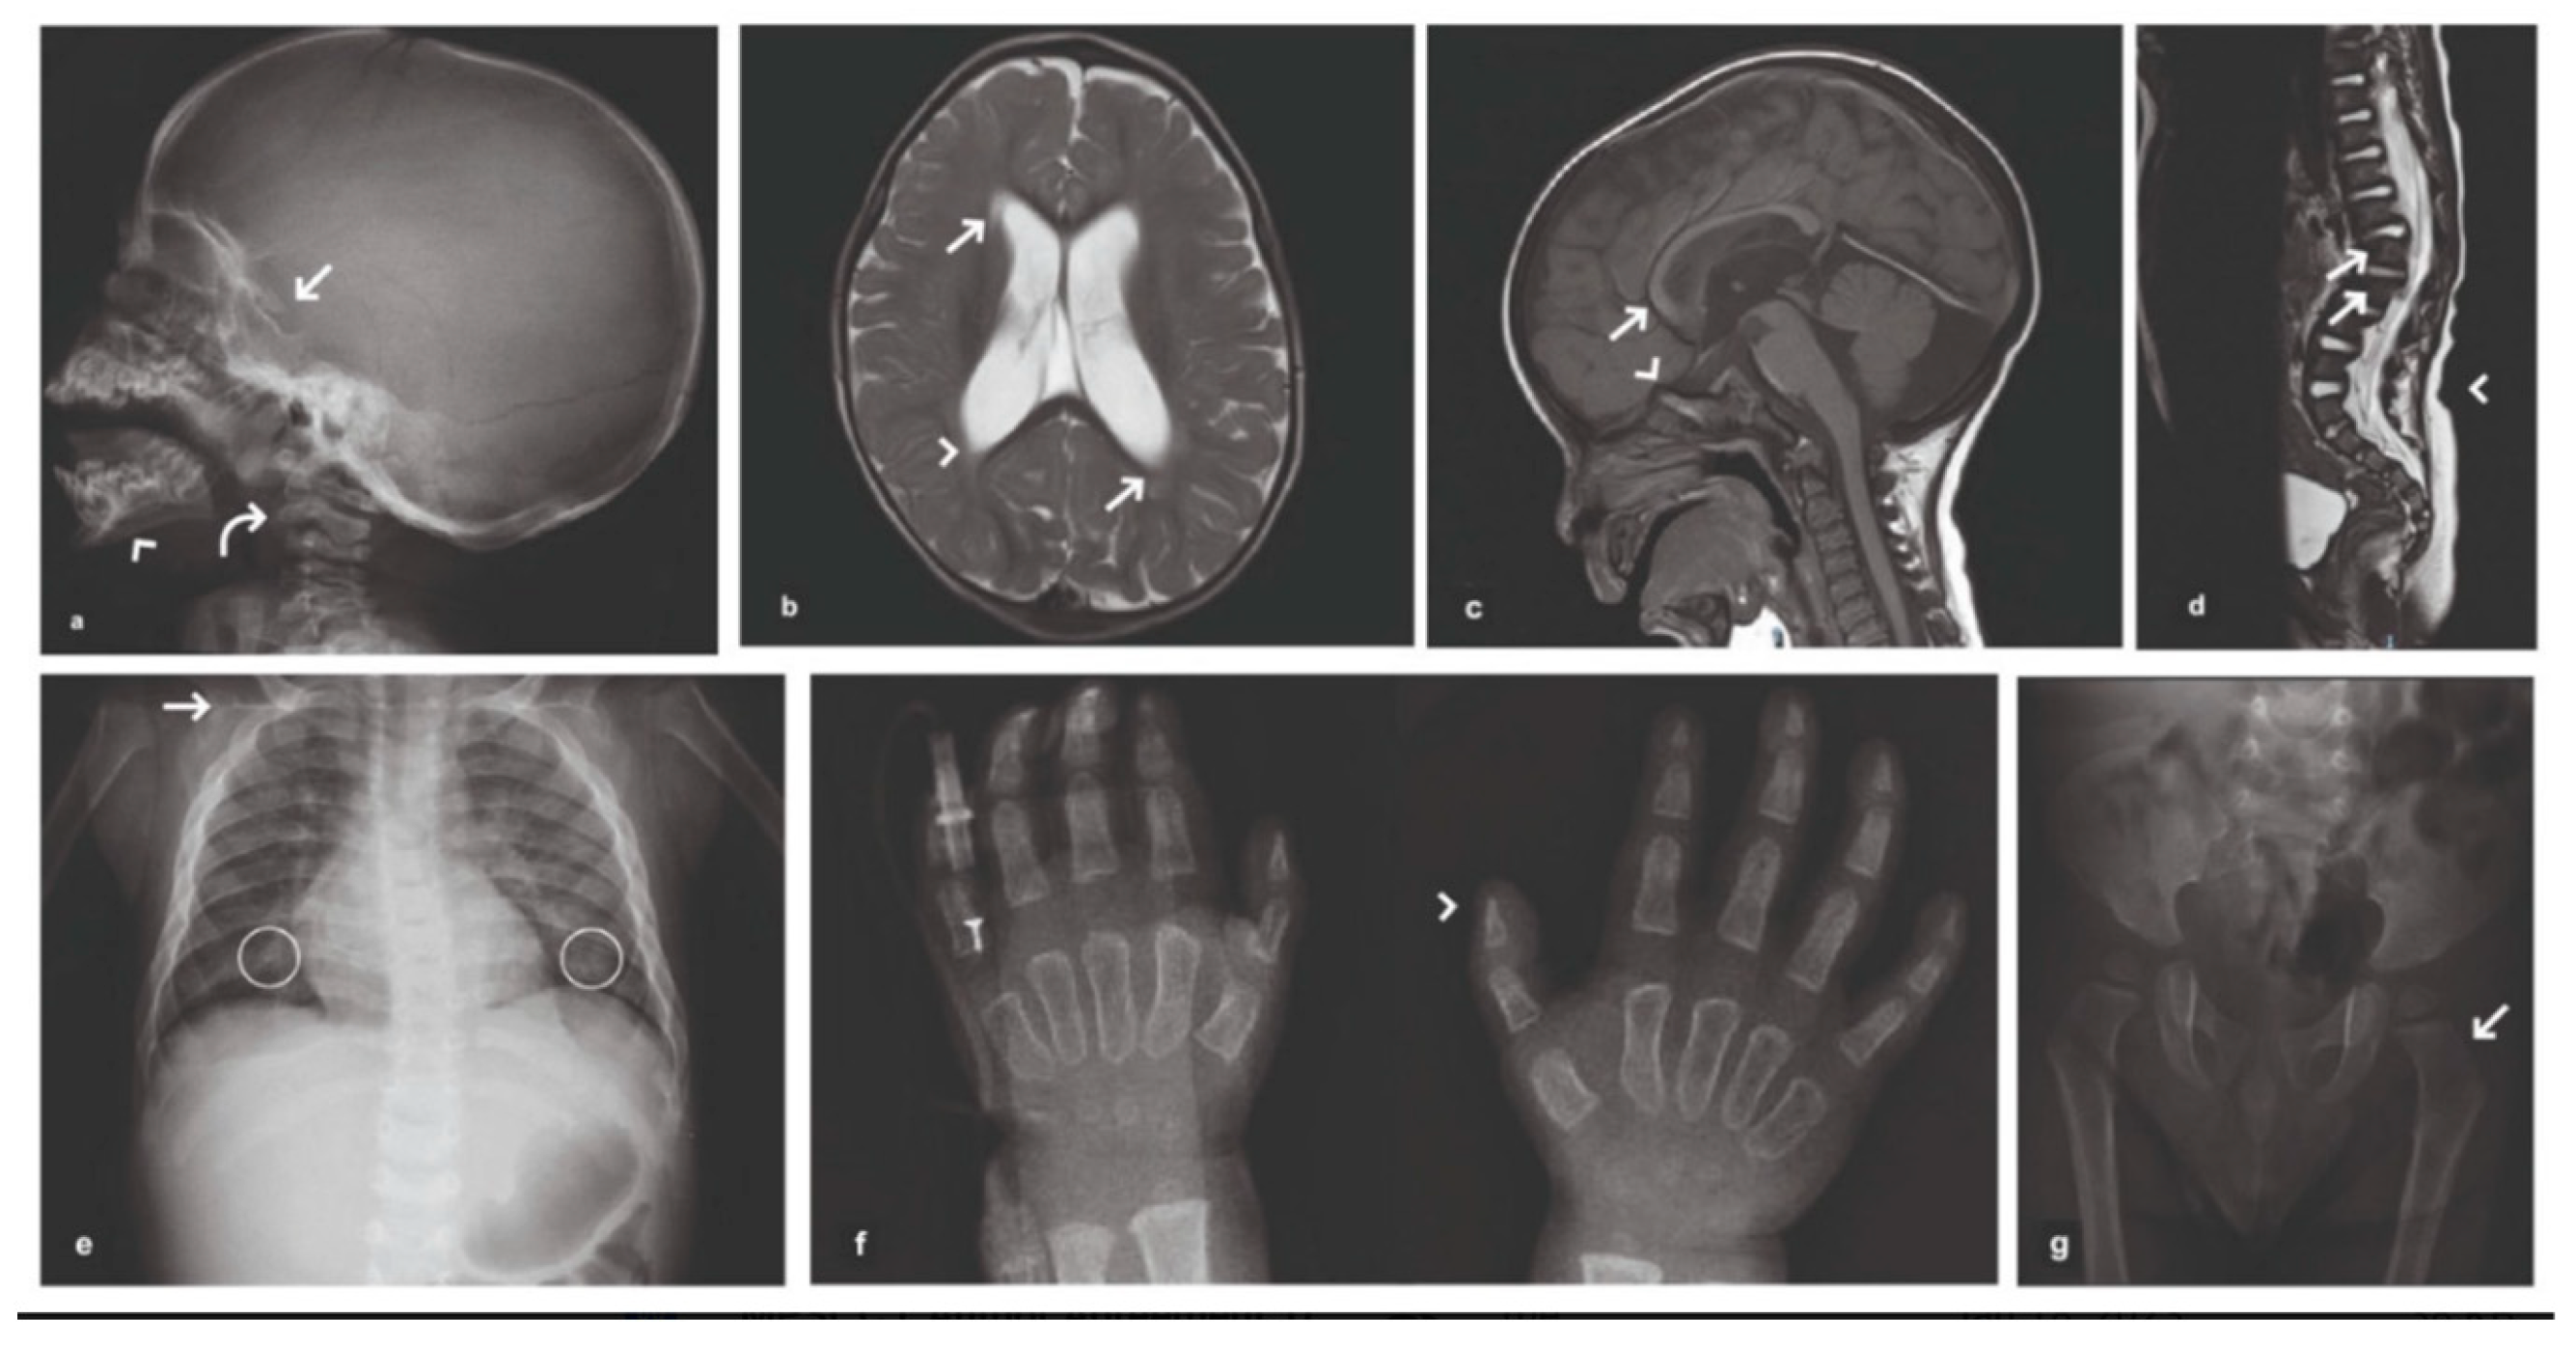

2. Case Presentation